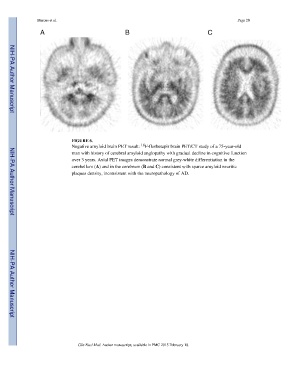

FIGURE 6.

Negative amyloid brain PET result: F-florbetapir brain PET/CT study of a 75-year-old

man with history of cerebral amyloid angiopathy with gradual decline in cognitive function

over 3 years. Axial PET images demonstrate normal grey-white differentiation in the

cerebellum (A) and in the cerebrum (B and C) consistent with sparce amyloid neuritic

plaques density, inconsistent with the neuropathology of AD.